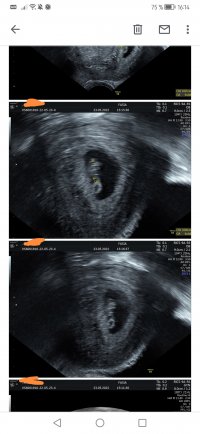

Er det noen som har vært på ultralyd rundt uke 7+6? Jeg har bestilt time til da og er så spent på hva vi får se! Gjerne sleng med bilde om dere har

Dette var vel 7+5, hode, rumpe, arm og fot ses her. Ikke mye en se så tidlig, men vi var for å se etter hjerteslag og det fikk vi se.